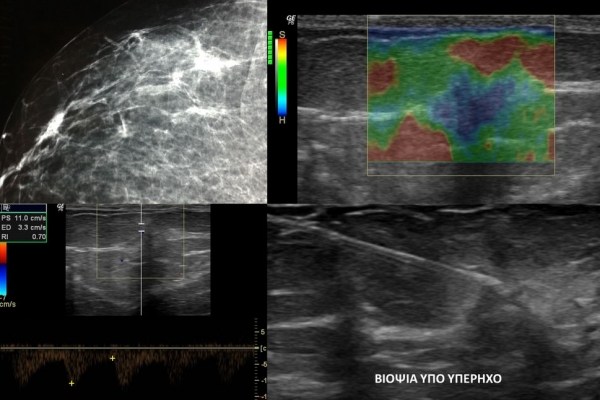

Η ελαστογραφία μαστού είναι μια σύγχρονη υπερηχογραφική μέθοδος που επιτρέπει τη διάκρισητων καλοήθων ογκιδίων από τους κακοήθεις όγκους.

Συνοπτικά ασκείται μια μικρή πίεση στους εντοπισμένους όγκους, μετρώντας την ελαστικότητα τους.

Ο καρκίνος γενικά εμφανίζει μεγαλύτερη σκληρότητα-ελαττωμένη ελαστικότητα σε σχέση με τα καλοήθη ογκίδια και επομένως η ελαστογραφία μπορεί να δώσει τις αναγκαίες πληροφορίες έτσι ώστε να μειώσει τις βιοψίες μαστού μόνο στις απολύτως απαραίτητες.